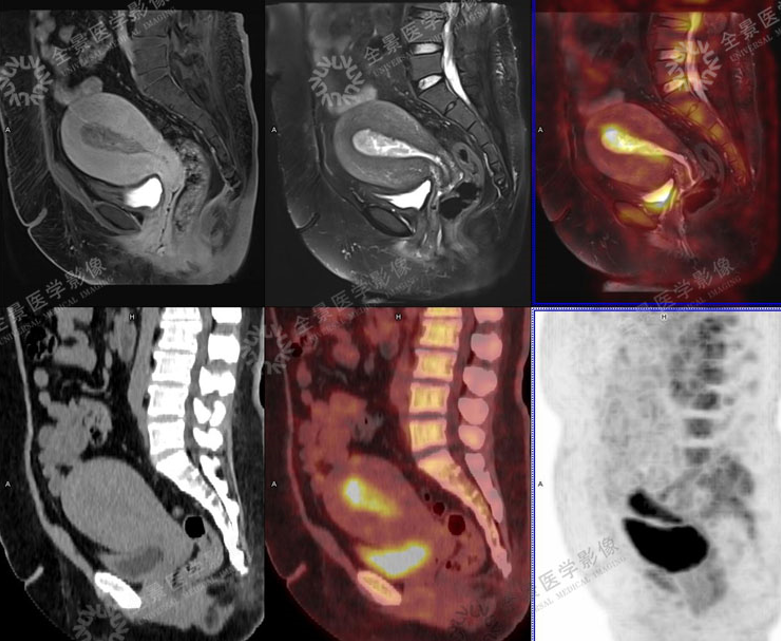

4. 妇科肿瘤

宫颈癌

病灶向上累及子宫峡部,向下累及阴道穹隆及相邻阴道壁,宫颈周围脂肪间隙清晰。

子宫内膜癌

对子宫肌层及周围结构侵犯进行临床分期